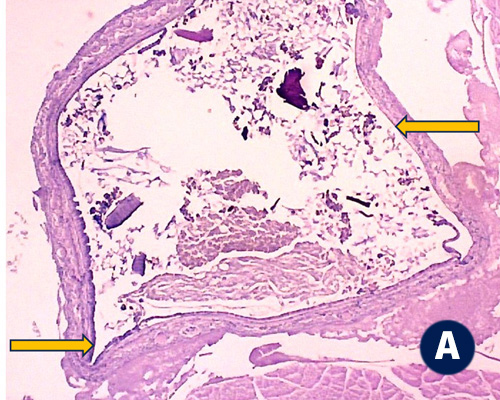

Un estudio realizado en camarones (Litopenaeus vannamei) de 2g de peso promedio inicial, en ocho réplicas de grupos de control no alimentados con PAQ-Protex (A), y grupos de tratamiento alimentados con PAQ-Protex a 2kg/TM de alimento (B), muestra una estructura intestinal mejorada de los camarones cuando se alimentan con PAQ-Protex (Datos internos de Phibro).

Camarones no alimentados con PAQ-Protex - Grado 0 (nivel bajo a sin pliegues intestinales):